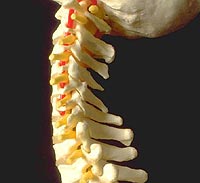

Investigadores británicos desarrollarán cementos óseos para fracturas de la columna vertebral

Leer más...